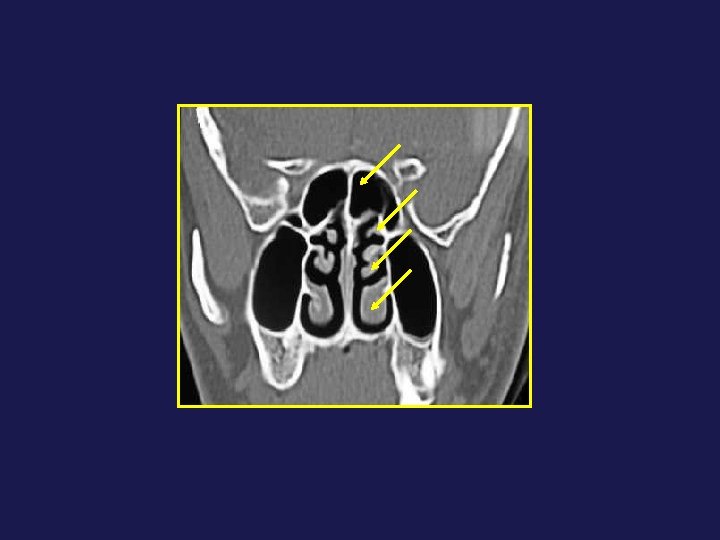

Le drainage se fait à travers un complexe anatomique : Tractus nasofrontal 2. Infundibulum

Le drainage se fait à travers un complexe anatomique : Tractus nasofrontal 2. Infundibulum frontal 3. Ostium frontal 8. Récessus frontal 1 2 4 7 3 8 5 9

Le drainage se fait à travers un complexe anatomique : Tractus nasofrontal 2. Infundibulum frontal 3. Ostium frontal 8. Récessus frontal 1 2 4 7 3 8 5 9 4 - Bec nasofrontal 5 - Agger Nasi 7 - Bulle ethmoïdale 9 - Racine cloisonnante du CM